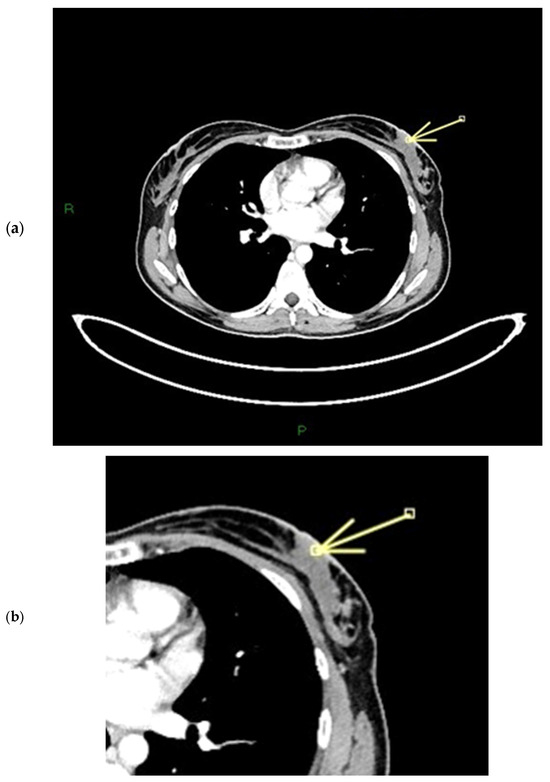

Figure 12.

(a–c) Patient’s name DN.A. The external quadrants of the right breast are occupied by a mass lesion with non-mass peripheral components, which infiltrates the nipple, retracting it. During ce-MR, we see a flat thickened right nipple, with SLE, NEZ, and marked patchy INE pattern of enhancement (arrows in a,b). In the ce-CT scan, the arrow shows enhancement of both the base and the body of the right nipple. Morphology is inverted, with skin thickening and ulceration (c).